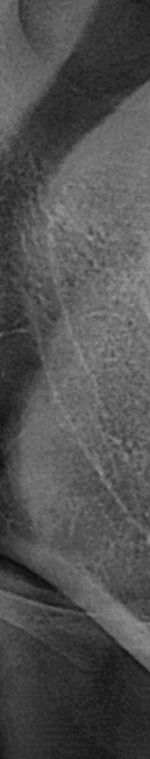

사랑니가 90도로 누워서 난 경우는 수평 매복, 뼈나 잇몸에 사랑니가 완전히 덮여서 아예 보이지 않는 경우는 완전 매복, 일부분만 잇몸이나 뼈에 덮여있는 경우 부분매복이라고 했어요. 대부분의 환자분이 이런 매복 중에 한 가지에 해당하기 때문에 시술이 매우 어려웠어요. 특히 사랑니 주변으로는 구강과 관련된 중요한 신경 조직이 인접하여 있기 때문에 고난이도 시술이라고 할 수 있었어요.

사랑니발치를 하기 위해서는 먼저 파노라마 x선 사진을 통해 발치 시 신경에 영향을 줄 수 있는지 확인하는 과정을 진행했어요. 이 과정을 통해서 충분히 의사와 상담을 한 후 처방전을 발급했어요. 이 때 처방전에는 항생제를 포함하여 발치 후 통증을 대비한 진통제를 처방했어요. 환자에게 충분히 설명한 후에 국소마취를 진행하고 마취가 된 다음에 절개를 최대한 덜 하는 방향으로 수술하여 사랑니를 발치했어요.